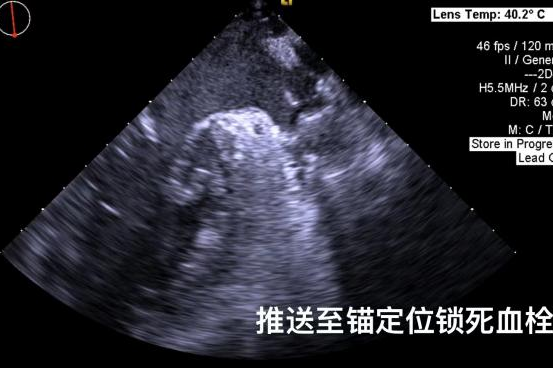

▲半发展固定伞,推送至锚定位锁死血栓

其中首场公开演示的左心耳血栓封堵病例拥有极高难度,患者术前TEE显示左心耳血栓形成伴机化,血栓位于心耳中段,近中端絮状物显著。封堵机遇只有一次,选型和操作稍有失误,城市增长手术风险。因而手术采取全麻,并装置了抗栓塞脑动脉;ぷ爸,以削减术中风险。通过TEE疏导下丈量左心耳大幼以及确认左心耳血栓地位,李岳春教授凭借自身丰硕经验最终决定使用LAmbre 2632型号,选取推送式植入法将左心耳血栓牢牢锁死于远端,并且封堵器一次成型,封堵成效极佳,实现后取出脑;ぷ爸,均未见血栓,顺利实现了此台高难度的手术,获得了学员们的一致认可。